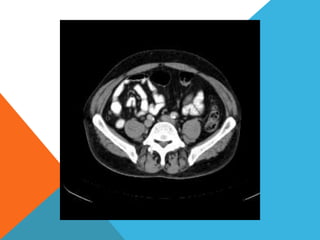

El paciente presentó síntomas de sangrado digestivo y pérdida de peso. Exámenes revelaron gastritis crónica asociada a H. pylori. Un tumor fue descubierto en una colonoscopia normal. La cirugía removió un tumor fibroide solitario, una rara neoplasia mesenquimal que usualmente crece lento y tiene bajo potencial de malignidad. El pronóstico después de la remoción quirúrgica es generalmente bueno.